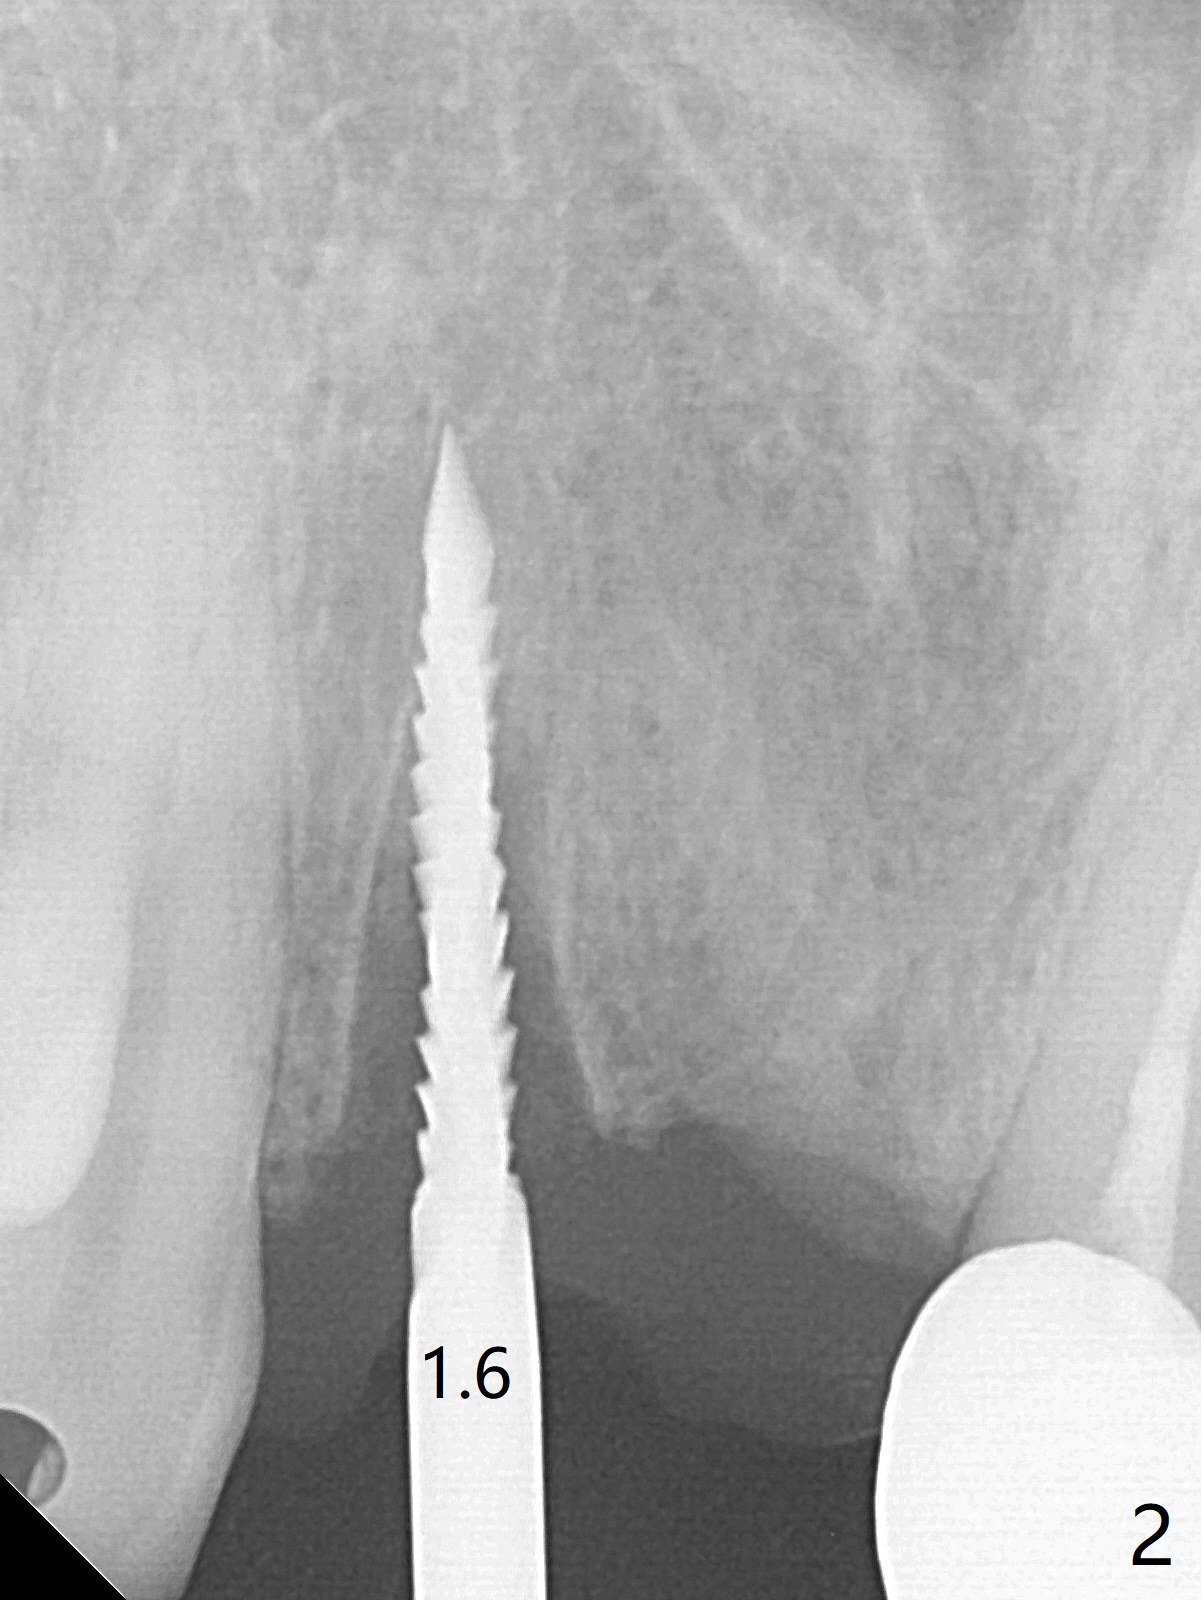

拆除部分桥发现:中,侧切牙牙龈红肿(图一),不利于切口和伤口愈合。不过还是在中切牙区切开,牙龈相当厚,有利于今后牙龈形成凹陷和乳头。坏消息是近远中距离太短,不利于植牙以及今后局部卫生维护,所以决定只在侧切牙种植(图二,三),完成钻洞后,颊侧根尖穿孔植骨,然后植入植体,即刻放置修复基台(图四 (*:牙龈乳头)),暴露基台牙龈缘,制作临时悬臂桥 (图五),两个中切牙牙冠长度差不多,插入临时桥时颊侧牙龈乳头基本形成(图六:*),缝合前颊侧,腭侧牙龈瓣下放置粘性骨块(图七,八:* )和PRF膜(图七:^)。最后使用牙周敷料。但愿术后牙龈炎症消失,形成良好牙龈乳头和pontic concavity。 其实由于口腔卫生习惯,术后十七天颊侧牙龈仍红肿(图九),而腭侧正常。如果口腔卫生改善而红肿依然存在,让实验室制作临时桥。术后一个月颊侧牙龈红肿好些(图十),好像骨粉丢失少许,可能与水枪使用有关。右上1牙冠显得太短(*)。也太肥大,因为右上1切缘太颊侧,与左上1对比(图十一:*)。由于颊侧牙龈(图十二:B)术中推向颊侧,与腭侧(P)牙龈之间放置大量粘性骨粉,术后一个月骨粉(<)形成牙龈,形成凹陷。颊侧萎缩不再明显了。右上1牙冠颈部多加些树脂,牙齿就显得长的多(图十三:箭头)。与侧切牙之间颈部故意留下间隙(*),让牙龈入位(空箭头),形成龈乳头。当右上1临时牙冠切缘(图十四:*)移到腭侧,外形改观不少。下次改善侧切牙唇侧。术后两个月三个星期牙龈红肿好像减轻,牙龈没有进入切牙间隙,干脆用树脂关闭(图十五:> <)。下次减少侧切牙切缘(^),适当增加中切牙长度(上提牙龈)。术后3.5个月植体好像整合,基台完全就位(图十六)。术后3.5个月Pontic凹陷形成,但是1,2之间龈乳头始终无法形成(图十七)。以后类似病例应该多种植一个。此例草率取模,可能需要临时粘固,观察植体近中颊侧所谓瘘道,必要刮治。由于比色不佳,需要实验室颜色更改,病人强化卫生,术后七个月,永久性牙冠粘固前,局部牙龈健康(图十八)。